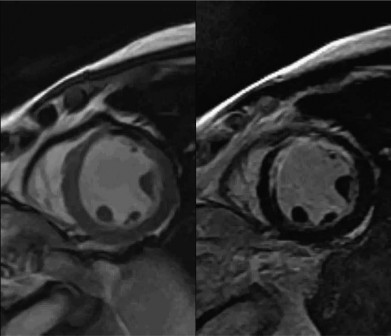

Hình 1.6: Kết quả MRI tim của một bệnh nhân có nhồi máu thành trước mạn tính

(Trái) Những đoạn mỏng, vô động được ghi nhận ở thành trước và trước vách, có nhồi máu xuyên thành.

(Phải) Dấu hiệu ngấm thuốc muộn minh hoạ mức độ lan rộng của nhồi máu xuyên thành khoảng 50% ở những đoạn cơ tim thành trước bên và trước vách.

“Nguồn: Garcia M. J. et al., (2020)” [53]